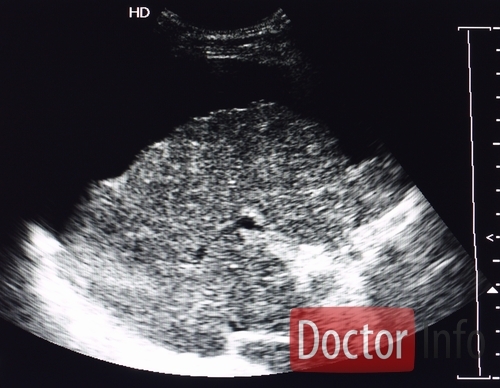

Для диагностики проводится подробный сбор анамнеза, осмотр больного, перкуссия (простукивание) живота в горизонтальном и вертикальном положении , определение флюктуации жидкости, УЗИ и КТ, сканирование печени и селезенки. С помощью допплерографии оценивают кровоток по портальной, печеночной и селезеночной венам. Желательно проведение диагностического парацентеза (пункцию брюшной полости) с обязательным исследованием асцитической жидкости.

Медицинские процедуры, проводимые при заболевании асцит: ЭКГ, УЗИ брюшной полости, Компьютерная томография, Магнитно-резонансная томография, Сканирование печени, Сканирование селезенки, УЗ-допплерография сосудов паренхиматозных органов в дуплексном режиме, Диагностический парацентез, Клинический анализ крови, Коагулограмма, Биохимический анализ крови, Рентген, Лапароскопия, Биопсия печени, Исследование асцитической жидкости, Спиральная компьютерная томография, Анализ мочи